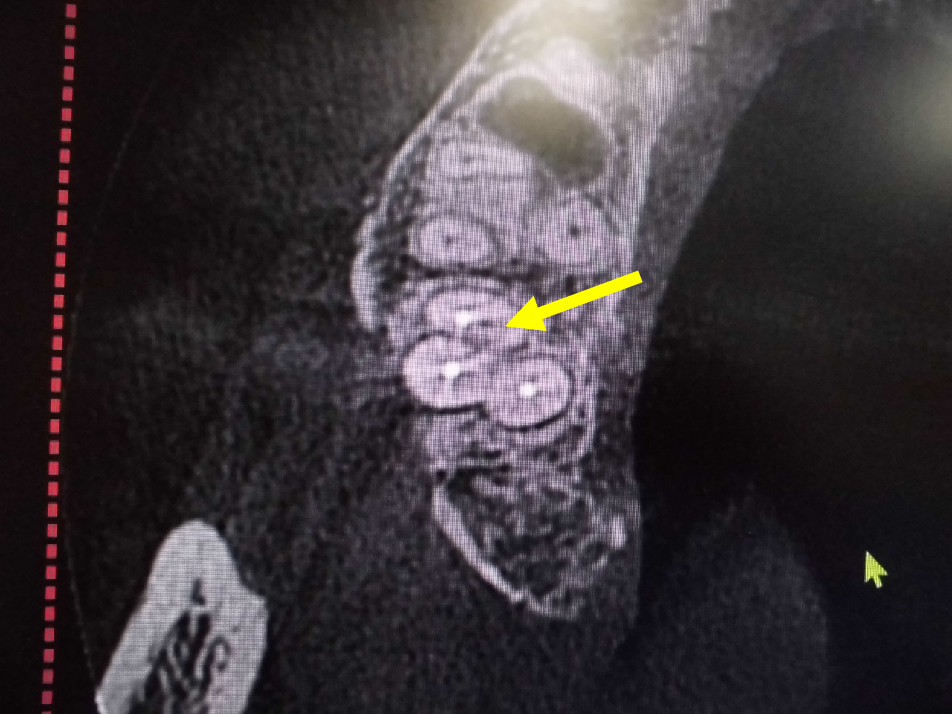

レントゲンでは不明な根尖病巣がCTでははっきり写ります。

同じ患者様です。根管が樋状根になっているのもわかります。